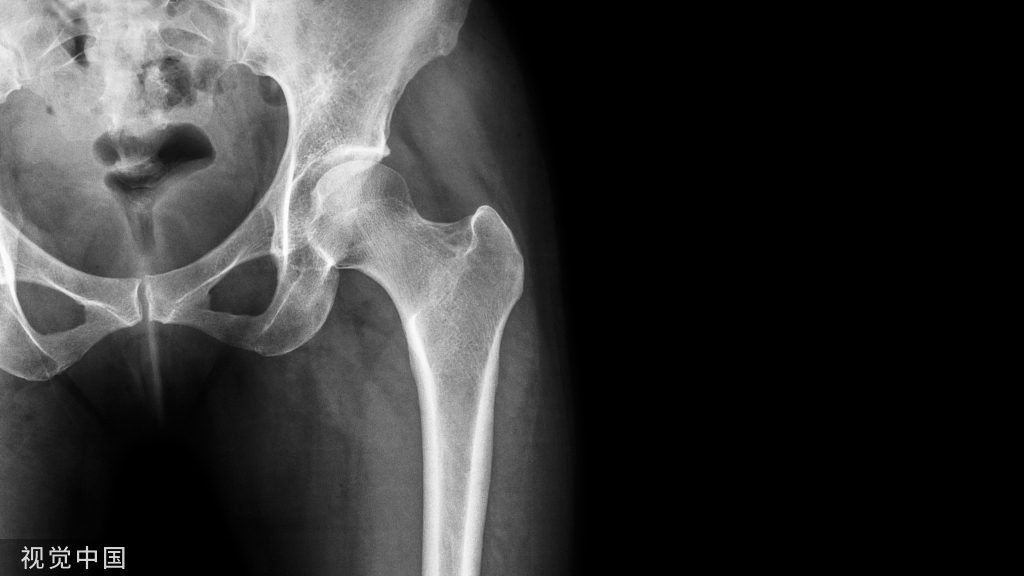

髓内钉断钉一般只有两种原因,承受了不该承受的应力!什么叫不该承受的应力呢?就是应力过大,突然的外伤导致断钉;载荷过多,骨折没有愈合但长期负重行走。

钉子在测试的时候都是在一定比较理想的状态,“解剖复位”或者部分解剖复位,“理想中的AO分型只有一个骨折线,没有移位。”

看过那么多文献,很少有髓内钉在测试的时候进行了异常状态的测试,比如:内外翻时候的应力循环载荷;不同复位不良情况下的应力循环载荷;进钉点错误,外侧壁骨折,内侧壁缺失的情况等等。

但是出现髋内翻、复位不良在手术中是十分常见的,这个情况下的应力相比解剖复位和相对解剖复位的应力大得多。